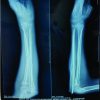

After the surgery, the wrist is placed in a splint or cast to prevent movement and support the initial healing process. Follow-up involves the use of sequential radiographs to evaluate the healing of the fracture and the correct positioning of any surgical implants. Dorsal distraction plating provides strong stabilization, allowing for prompt movement and restoration of function. Physical therapy is started once X-ray imaging confirms that the wrist has healed enough to regain its range of motion and strength. Subsequently, after the removal of the implant, adhesiolysis is carried out during the surgery to regain the mobility of the wrist joint. Dorsal distraction plating X-rays (Fig. 1, 2, 3, 4). ExFix X-rays (Fig. 5, 6, 7, 8, 9).